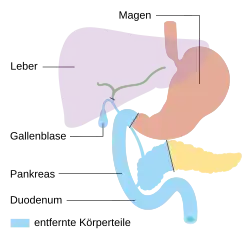

Es ist sinnvoll, möglichst einen Teil des Organs zu erhalten und wieder mit dem Darm zu verbinden. Je nach Ort des Tumors wird deshalb die rechtsseitige Teilresektion (Duodenopankreatektomie, mehrere Varianten), eine mittlere Teilresektion, eine linksseitige Teilresektion (Pankreasschwanzresektion, meist mit Entfernung der Milz) oder eine Totalresektion (vollständige Entfernung) der Bauchspeicheldrüse durchgeführt, meist einschließlich aller regionären Lymphknoten. Der Magen und der Gallengang müssen wieder mit dem Darm verbunden werden. Man verwendet dafür entweder eine oder mehrere hochgezogene Dünndarmschlingen, die spannungsfrei angeschlossen werden. Bei der Verwendung mehrerer Dünndarmschlingen werden diese rekonstruiert nach der klassischen von César Roux erdachten Methode. Nach Teilresektion kann der Ausführungsgang des belassenen Rests der Bauchspeicheldrüse sowohl mit dem Dünndarm als auch mit dem Magen verbunden werden.

Pylorus-erhaltende Teilresektion

Pylorus-erhaltende Teilresektion -

Duodenopankreatektomie nach Whipple

Duodenopankreatektomie nach Whipple -